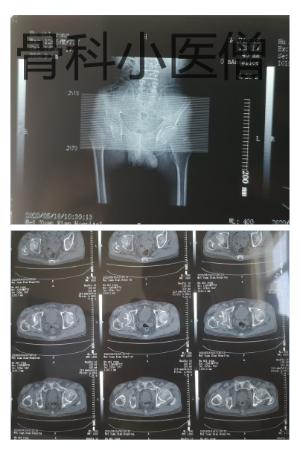

我科室值班医师接诊后仔细查体、行相关检查后明确诊断,原来胡大爷是右侧“大胯”骨折了,具体就是我们医学上说的“股骨颈骨折”,属于髋部骨折的一种常见类型。

术前CT检查明确股骨颈骨折。